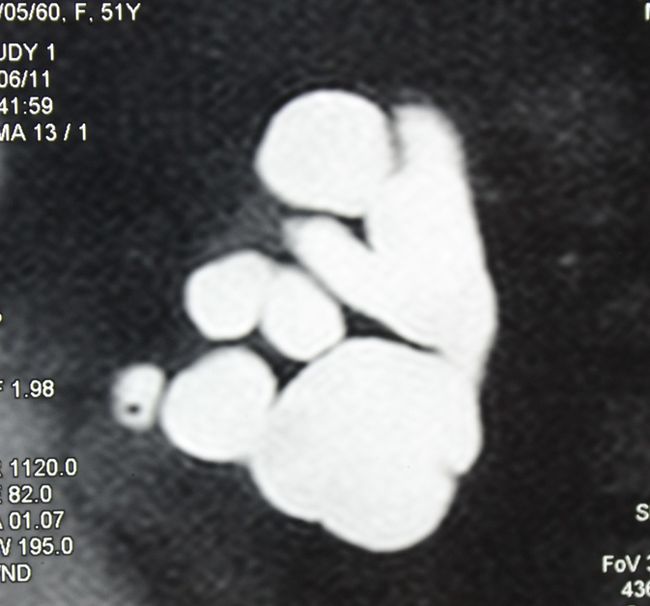

Гидронефроз III. Лапароскопическая нефрэктомия справа

Лапароскопическая нефрэктомия